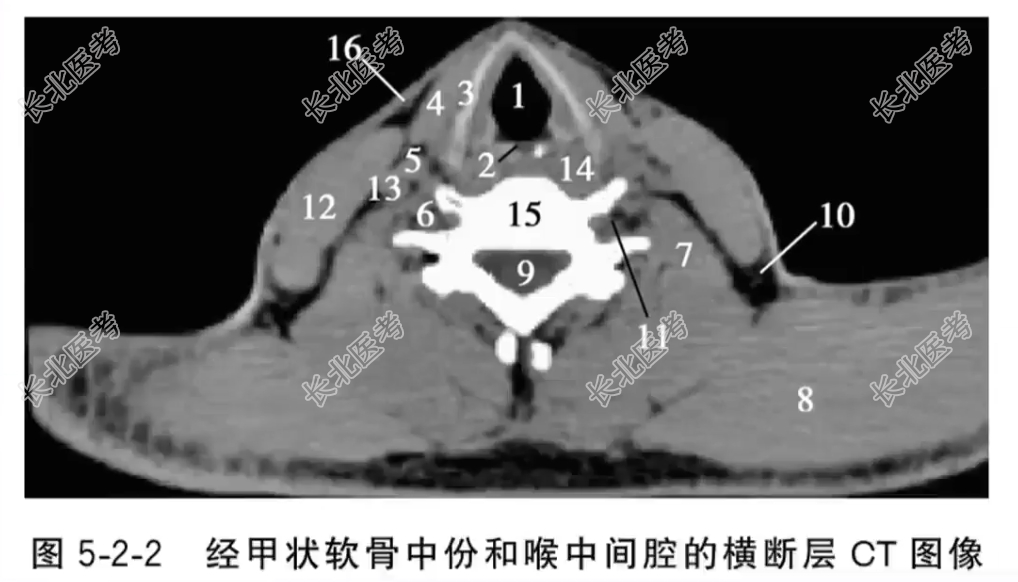

- 单项选择题经甲状软骨中份和喉中间腔的横断层CT图像中,标记为15的结构是

A、第6颈神经

B、第6颈椎体

C、喉中间腔

D、脊髓

E、颈长肌